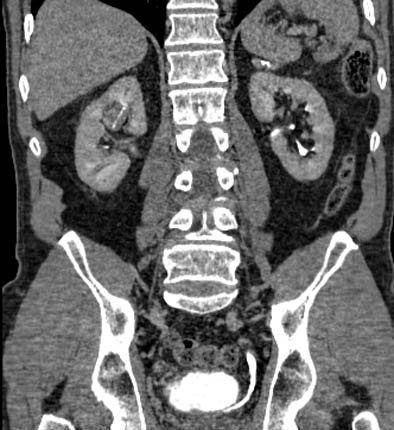

| Postprocessing or reformatting images may obscure the diagnosis. TCC clearly seen on axial CT (above) and on coronal multiplanar reformat below. But even a thin-slab MIP reformat masks detection of the right-upper-pole TCC (bottom). Images courtesy of Dr. Nigel Cowan. |